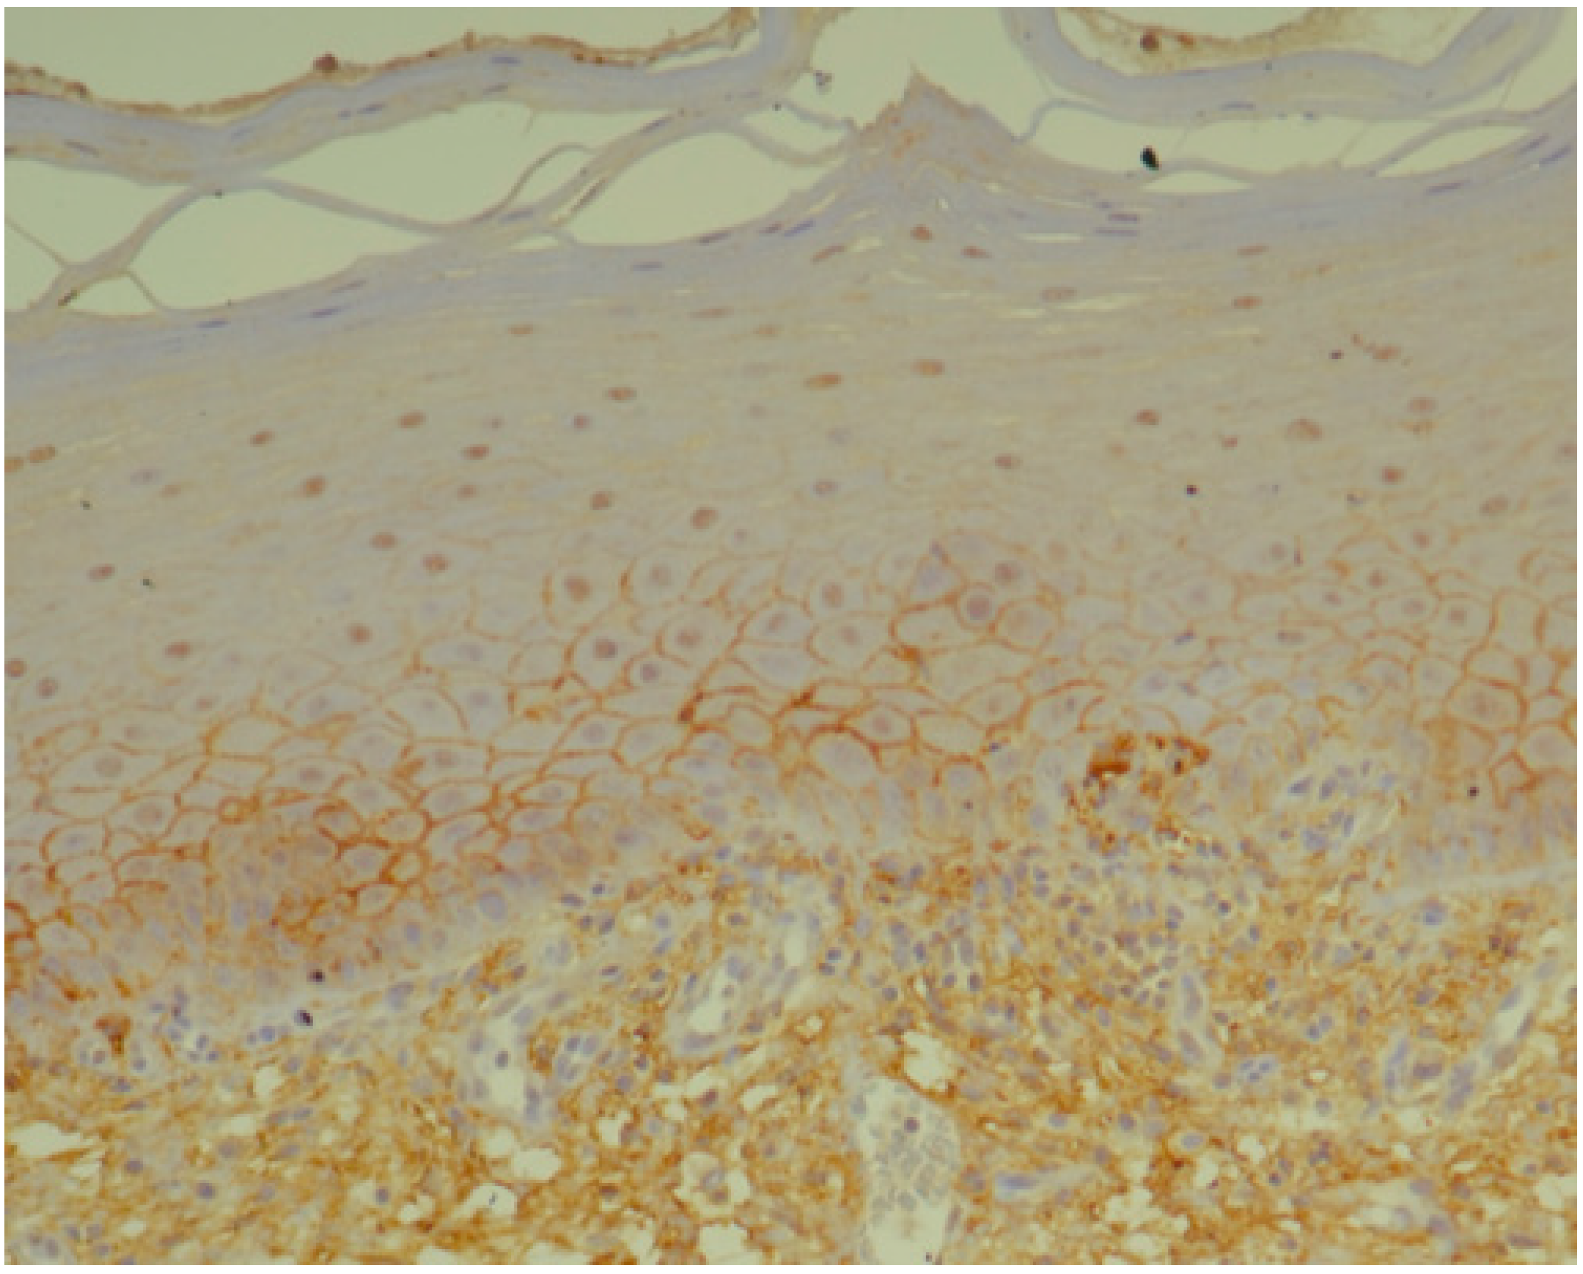

3.1. Histopathology and Immunohistochemistry

2.2. Histopathology and Immunohistochemistry